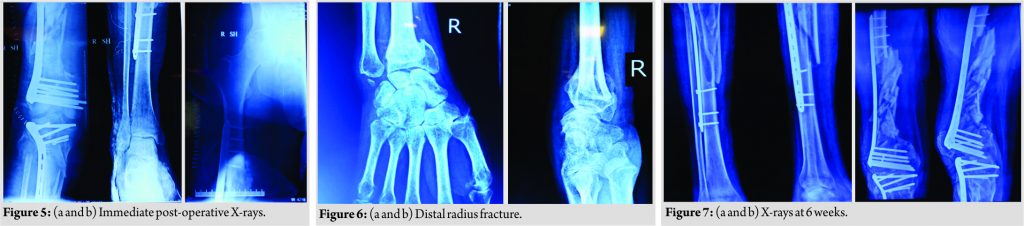

After splitting the distal part of tensor fasciae latae, the distal locking screws were removed.Since the plate was bent, a bone hook was used to pull out the proximal end of plate laterally. Now, the position of the proximal screws was marked under C-arm control using an artery forceps. Each screw head was cleared causing minimal muscle damage and they were removed in a minimally invasive fashion, thus preserving the biology of zone of comminution and the plate was gently levered out. Following implant removal, we identified that there was another fracture line in coronal plane just posterior to plate application in the articular block which was identified as lateral condyle Hoffa fracture. The articular reconstruction was first done and the Hoffa fracture was fixed using single partially threaded cancellous screw. Manual linear traction was applied to the limb after reconstructing articular block and grossly comminuted fragments were seen to be aligned, so no attempt was made to open the comminuted area. The length of the limb was maintained by giving linear traction and an electrocautery was used to ensure that the center of femoral head, patella, and second toe lie in same line and checked under C-arm to maintain the correct rotation of the limb. The longest available distal femur locking plate (A.O SYNTHES) in the set was slid in a MIPPO fashion bypassing the zone of comminution after reconstructing the articular block. Same incision was extended below knee to expose proximal tibia and the longest available lateral tibia locking plate(A.O SYNTHES) was slid in a MIPPO manner bypassing the comminution. Now, after fixing both the fractures, the knee was examined for ligamentous instability and it was found to be globally unstable in both the planes. Considering the gross comminution in both femur and the tibia, and the being an open fracture, it was decided to wait for ligamentous reconstruction till bony union was achieved. Wound was sutured in layers over negative drain and a long knee brace was given to the patient since the knee was unstable in both the planes.The patient was shifted out of theater in an intubated state. Immediate post-operative X-rays revealed satisfactory alignment of both fractures, (Fig. 5). During the next 7 days, the patient remained intubated and during this period, the passive movement of joints was given, the limb was elevated and the stitch line was carefully monitored. Once the patient was extubated on the 8th day, it was found that there was an associated foot drop which was missed preoperatively since the patient was in an intubated state. The foot drop splint was applied accordingly and physiotherapy in the form of guarded ROM and muscle strengthening exercises was started. We could not ambulate the patient as he had another fracture in the wrist in the recent past, (Fig. 6).

The wound healing was bit delayed but it was ultimately uneventful. An X-ray was taken at 6 weeks post-operative which revealed satisfactory alignment (Fig. 7) and toe touch weight-bearing with long knee brace was started under supervision of trained physiotherapists. The patient was further followed up at 1 month interval and during this rehabilitation period, special attention was given to his psychiatric care. At the latest follow-up of 6 months, the patient had radiological and clinical evidence of union (Fig. 8). At the last available follow-up,the ligamentous instability still persisted, and with long knee brace, he was able to stand and walk. The foot drop was also recovering and there was no extension lag and knee flexion was upto 90° (Fig. 9). At this moment, he was properly counseled and explained in detail about all the available options in the form of arthrodesis, hinged knee arthroplasty, and ligamentous reconstruction, but the patient opted for non-operative management in the form of long knee brace for the time being.